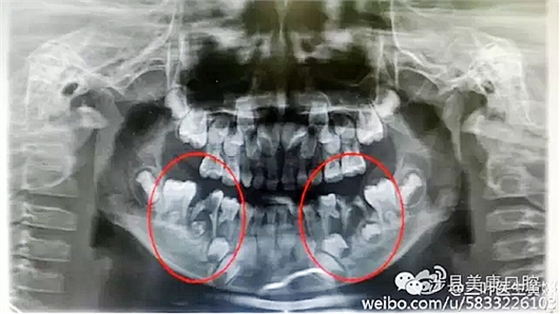

普通家長看了這張牙片估計能看出來孩子的牙不好,但是究竟不好到什么程度呢,讓葉子姐告訴大家:

上圖孩子的乳牙感染已經(jīng)將下面骨感染到吸收消失,并且直接影響到了下面的恒牙胚,家長們上點心吧。那些說乳牙不用治療,換牙就會好的人(包括醫(yī)生)還是睜開眼睛看看吧,不要自欺欺人,更不要用自己的錯誤誤導(dǎo)他人誤導(dǎo)大眾。

網(wǎng)友又不明白了,什么叫吸收消失?看x片看不懂哎......

黑色部分表示那里的骨頭感染已經(jīng)爛沒有了,消失了,牙胚應(yīng)該在健康頜骨里孕育生長發(fā)育,現(xiàn)在在感染的病灶里生長,在膿水里侵泡。

又有好奇網(wǎng)友問他怎么有那么多牙?

乳牙下面有恒牙孕育著。